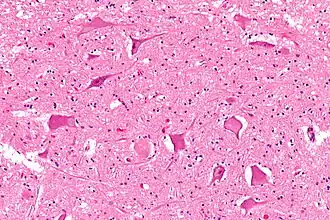

Idiopathic brainstem neuronal chromatolysis

Severe neuronal chromatolysis has been detected in the brainstems of adult cattle with the neurodegenerative condition known as idiopathic brainstem neuronal chromatolysis (IBNC). The symptoms of IBNC in cattle are clinically similar to those characterized by bovine spongiform encephalopathy, otherwise known as mad-cow disease. These symptoms included tremor, lack of muscle movement coordination, anxiety and weight loss.[17] At the cellular level, IBNC is marked by the degeneration of neurons and axons within the brainstem and cranial nerves. The disease also has a significant correlation with abnormal labeling for prion protein (PrP) in the brain. IBNC has been characterized by severe neuronal, axonal, and myelin degradation, accompanied by non-supportive inflammation and changes in spongiform of various regions of grey matter. A significant loss of neurons due to hippocampal degeneration has also been observed. The degenerate chromatolysis neurons seldom showed intracytoplasmic labeling for PrP.[18]